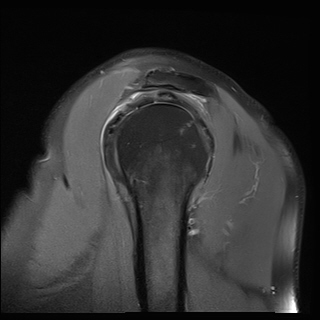

±Ø»ó°Ç ÆÄ¿­, Á¡¾×³¶¿°, °ßºÀÇÏ °ñ±Ø

¹æ»ç¼±»çÁøÀ̳ª ÀÚ±â°ø¸í°Ë»ç¿¡¼­ °ñ±ØÀÌ °üÂûµÇ°í ±Ø»ó°Ç ÆÄ¿­ÀÌ ÀÖ´Â °æ¿ì °Ë»ç¿¡¼­ º¸ÀÌ´Â

°ñ±ØÀÌ ±Ø»ç°ÇÆÄ¿­ÀÇ ¿øÀÎÀ̶ó°í ÃßÁ¤ÇÒ ¼öµµ ÀÖ´Ù.  ±×·¯³ª ±Ø»ó°ÇÆÄ¿­ÀÌ Ç¥Ãþº¸´Ù´Â ½ÉÃþ¿¡¼­

´õ ¸¹ÀÌ ¹ß»ýÇϰí Áõ»óÀ» ÀÏÀ¸Å°Áö ¾Ê´Â °ñ±ØÀÌ ¸¹Àº Á¡À» °í·ÁÇÒ ¶§ °Ë»ç¿¡¼­ º¸ÀÌ´Â °ñ±ØÀ»

Ä¡·á(°ßºÀ¼ºÇü¼ú)ÀÇ ´ë»óÀ¸·Î ÇÏ´Â °ÍÀº Çϸ®ÀûÀÎ °áÁ¤ÀÌ ¾Æ´Ï´Ù. ÀÌ È¯ÀÚÀÇ °æ¿ìó·³ ±Ø»ó°Ç

³»ÃøÀÇ ºÎÁ¾°ú Ç¥Ãþ ¶Ç´Â ÀüÃþ ÆÄ¿­ÀÌ ÀÖÀ¸¸é¼­ Á¡¾×³¶ÀÇ ºÎÁ¾°ú Ãæµ¹°Ë»ç ½Ã Ãæµ¹ ¼Ò°ßÀ» º¸ÀÌ´Â °æ¿ì¿¡

¹æ»ç¼±À̳ª ÀÚ±â°ø¸í°Ë»ç¿¡¼­ º¸ÀÌ´Â °ñ±ØÀÌ ±Ø»ó°Ç ÆÄ¿­ÀÇ ¿øÀÎÀ¸·Î ÃßÁ¤ÇÒ ¼ö ÀÖ´Ù.